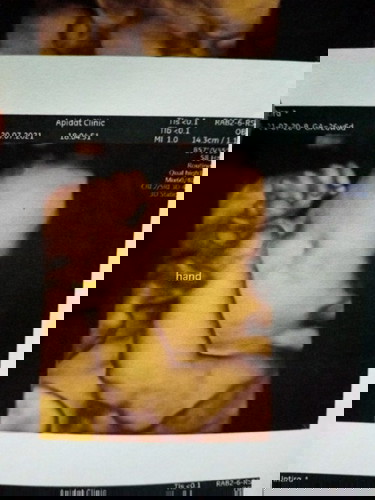

ตอนนี้อายุครรถ์34วีค ไม่เคยตรวจดาวซินโดม เลยคะ เคยแต่อัตตร้าซาวว์อย่างเดียว คือกังวลมากคะกลัวร้องจะเป็นดาวน์ซินโดรม แต่คุนหมอบอกน้องปกติทุกอย่างเลย แต่แม่แอบกังวลไปนิดนึ่ง เพราะตอนนั้นค่าใช้จ่ายสูงมาก แม่เคยมีประสบการไม่คะมาเล่าให้ฟังหน่อยคะ กังวนมากเลยตอนนี้